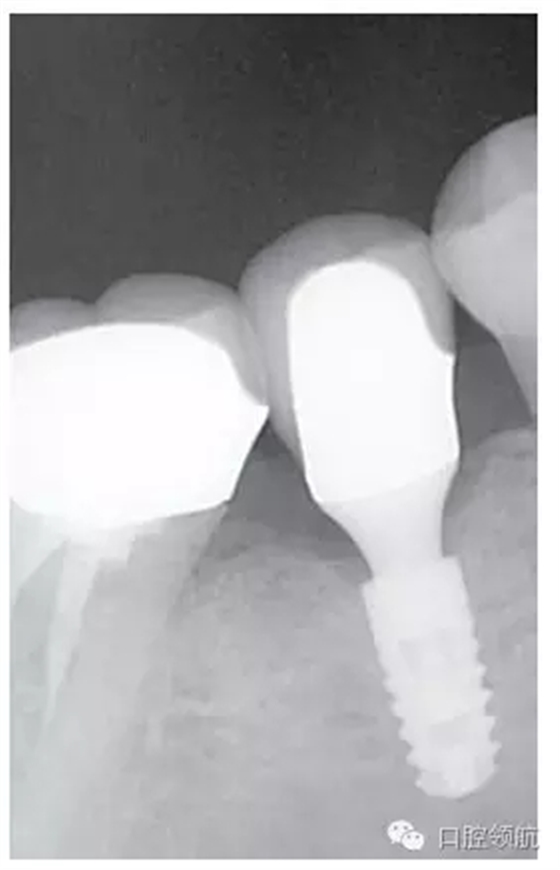

圖1 (左下第五顆牙) 部位,最終的上部修復(fù)體戴入完成時(shí)的狀態(tài)。

種植體的基臺(tái)與上部修復(fù)體的密合性,通過(guò)口腔X線片進(jìn)行檢查,確認(rèn)種植體周圍有殘留的粘接劑(圖2),使用探針等器械盡力清除剩余粘接劑,避免預(yù)后不良因素的產(chǎn)生。然后,通過(guò)X線片從投照的方向檢查確認(rèn)剩余的粘接劑,完全沒(méi)有殘留粘接劑的實(shí)際狀態(tài)(圖3)。